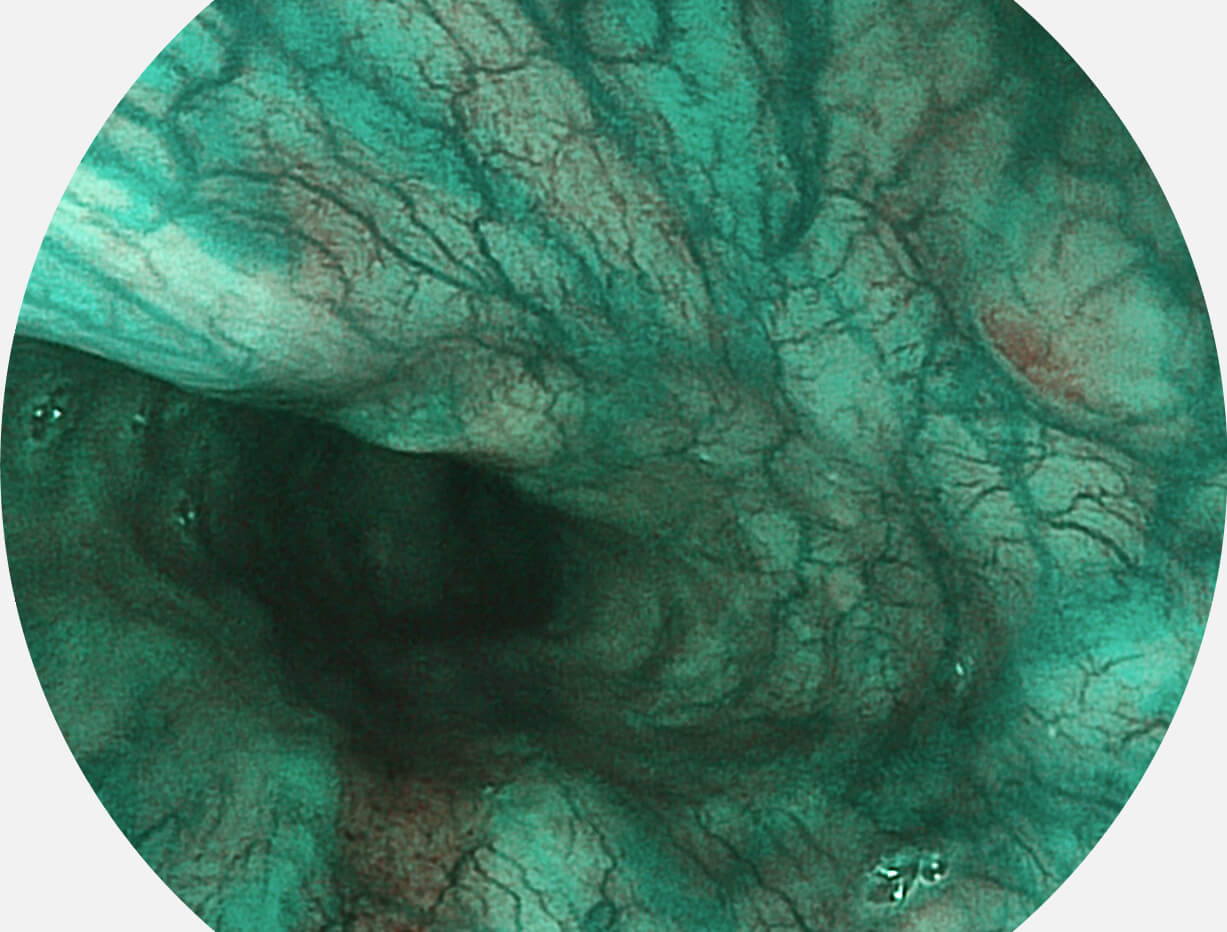

白光图像

白光图像

SFI图像

SFI图像

白光图像

白光图像

SFI图像

SFI图像

白光图像

白光图像

SFI图像

SFI图像